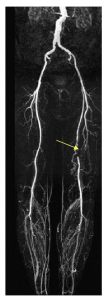

Ces techniques non invasives permettent une cartographie préthérapeutique souvent suffisante pour envisager un geste de revascularisation endovasculaire ou chirurgicale (figures 38.1 à 38.3). Les deux techniques ne nécessitent pas de ponction artérielle et l’angio-IRM ne nécessite pas d’exposition aux rayons X, ni l’utilisation de produits de contraste iodés.

Fig. 38.2 Exemple d’angio-IRM des membres inférieurs montrant une occlusion de l’artère fémorale gauche avec revascularisation par le réseau collatéral de l’artère poplitée sus-articulaire.

Source : CERF, CNEBMN, 2022.

Les techniques d’angio-IRM (cf. figures 38.1 et 38.2) ou d’angioscanner (cf. figure 38.3) mettent en évidence des sténoses ou des occlusions artérielles ainsi que le développement de voies de dérivation pour compenser l’hypoperfusion en aval.

Les différences entre les deux sont les suivantes :

- les calcifications artérielles ne sont pas visualisables en IRM ;

- l’angio-IRM a tendance à légèrement surestimer les degrés de sténose ;

- les plaques athéromateuses sont parfois mieux analysées en angioscanner grâce aux reconstructions dans l’axe des vaisseaux.